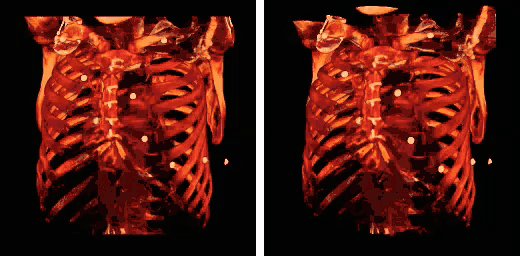

Human rib cage - CT scan (parallel projection (left) and perspective projection (right)) -

3D model of rib cage -